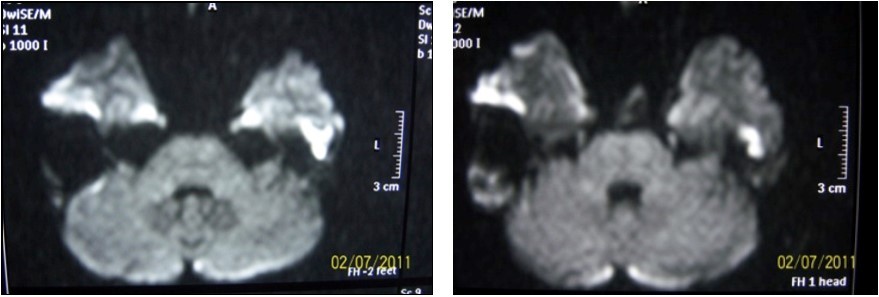

High intensity signals on diffusion MRI were considered to be supportive for cholesteatoma (Figure 3). 24 of patients (72.7%) were detected as cholesteatoma positive while 9 of them (27.3%) were negative on diffusion MRI (Table 1).

Figure 3.Diffusion MRI image of cholesteatoma

20 of 24 (83.3%) patients who had signs of cholesteatoma on preoperative diffusion MRI were positive intraoperatively while the remaining 4 (16.7%) were negative. 5 of 9 (55.4%) patients who had no evidence of cholesteatoma on MRI were positive intraoperatively while 4 (44.4%) were not (Table 1). There was no significant result obtained in terms of impact of diffusion MRI on detecting intraoperative cholesteatoma (p=0.09). In terms of indicatory strength of positive physical examination findings over presence of intraoperative cholesteatoma, sensitivity was found to be 96% whereas specifity was 87.5%, positive predictive value was 96% and negative predictive value was 87.5%. The area below the curve on ROC curve analysis was calculated as 98% (Table 3) (Figure 4).